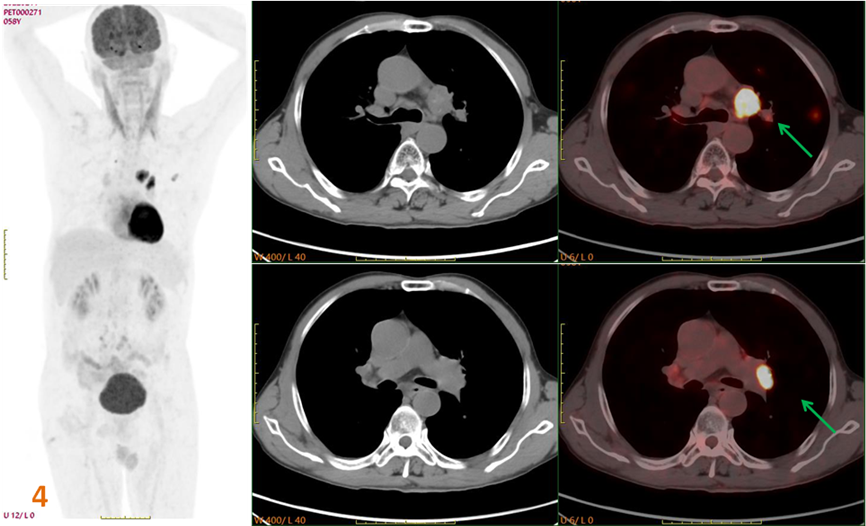

為明確原發(fā)灶行PET-CT進(jìn)一步檢查(圖3、4)。PET/CT示:左肺上葉不規(guī)則囊性灶(SUVmax約5.3),左肺門、主動脈弓下高代謝病變(SUVmax約12.1);診斷為左肺上葉癌并多發(fā)轉(zhuǎn)移。

圖3、4. 左肺上葉不規(guī)則囊性灶(黃箭),SUVmax約5.3;左肺門、主動脈弓下高代謝病變(綠箭)SUVmax約12.1。

后行CT引導(dǎo)下經(jīng)皮肺穿刺活檢術(shù),病理證實(shí)為鱗狀細(xì)胞癌。